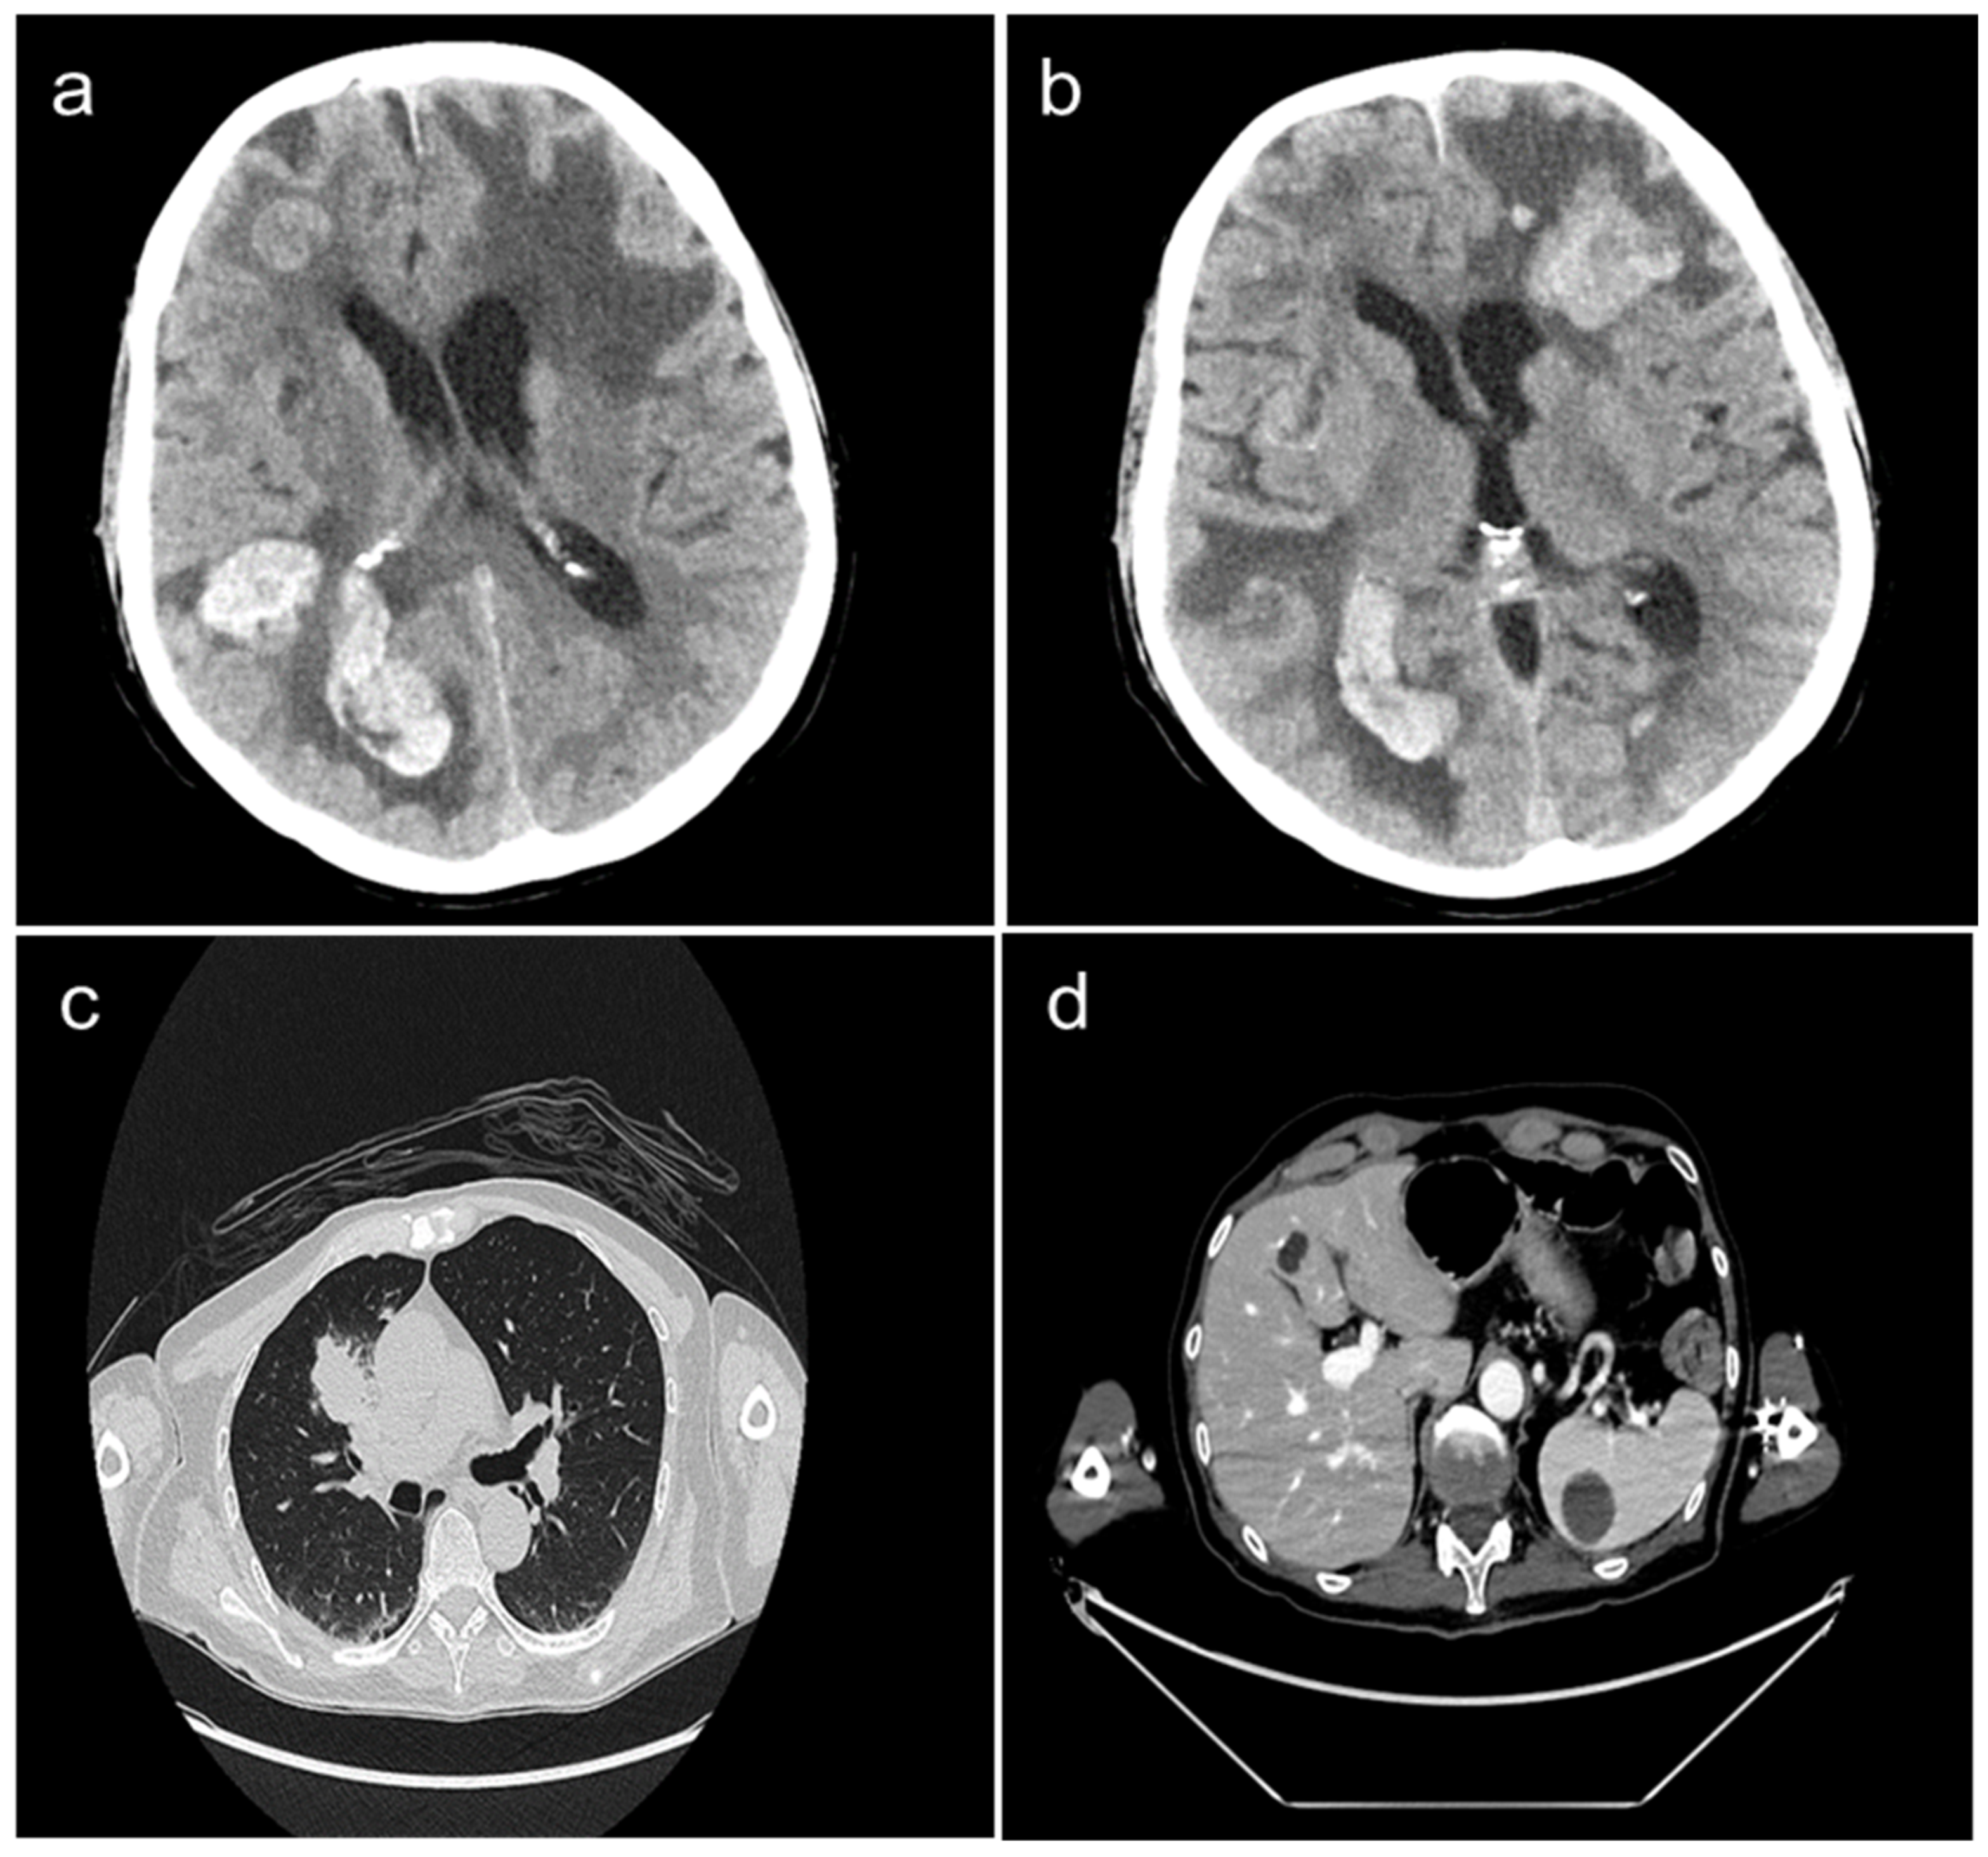

2. Case Presentation